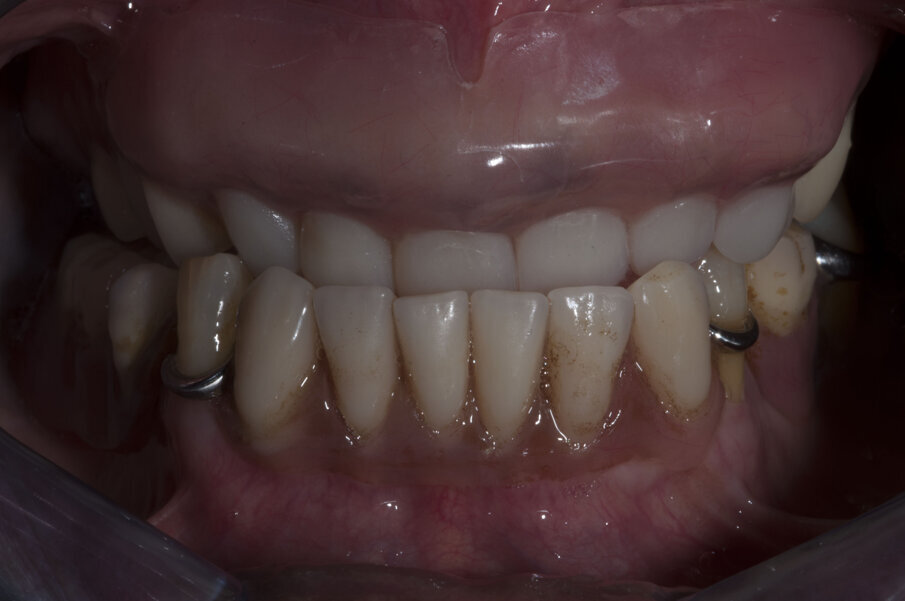

Il primo passo per riabilitare la paziente è stato comunque la sostituzione della protesi totale con una nuova più congrua, questo ha portato alla correzione sia della classe scheletrica non corretta che della VDO, fonte di disagio e sofferenza. L’esame extra-orale evidenziava questo dettaglio e come questo influenzasse il sorriso della paziente (Figg. 5-7).

La nuova protesi totale provvisoria ha portato immediatamente un miglioramento funzionale ed estetico, con un notevole beneficio psicologico sulla paziente ed un enorme vantaggio per il prosieguo della terapia (Figg. 8-10). Il nuovo montaggio con denti di maggiori dimensioni ed una differente occlusione ha conferito un miglior supporto al labbro superiore ed una migliorata estetica del sorriso (Fig. 11). Alla luce della nuova situazione, accettata e gradita dalla paziente, si è incominciato a pianificare la procedura chirurgica. Avendo la CBCT evidenziato dei volumi ossei adeguati (Fig. 12), si è proceduto allo studio del caso mediante un software di chirurgia guidata (Simplant, Dentsply-Sirona) (Figg. 13, 14).